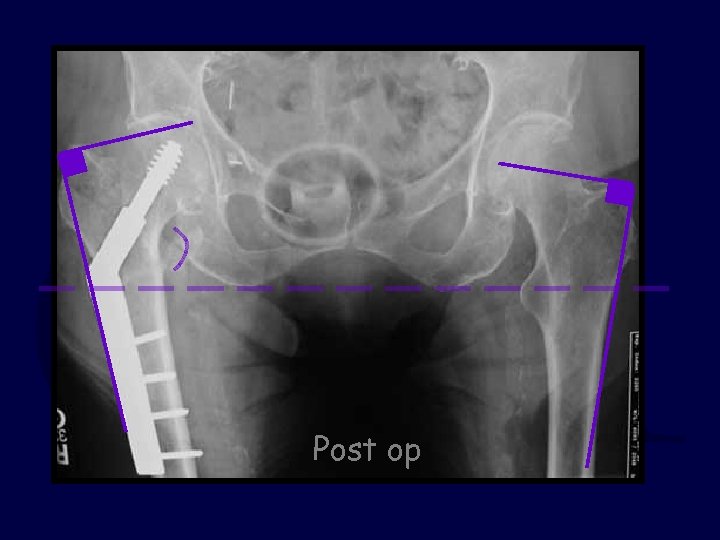

81 y. o. female slipped & fell 3 part IT fx Discuss: Did the surgeon do a good job? Yes or No Post-op X-rays

Did the surgeon do a good job? · Yes · No Answer before advancing.

Now, consider specifically: A. The reduction is satisfactory B. The TAD (screw position) is OK C. Both are satisfactory D. Neither are satisfactory …Choose Best Answer

Post op

The TAD was acceptable but the reduction was grossly short

Did the surgeon do a good job? · Yes · No